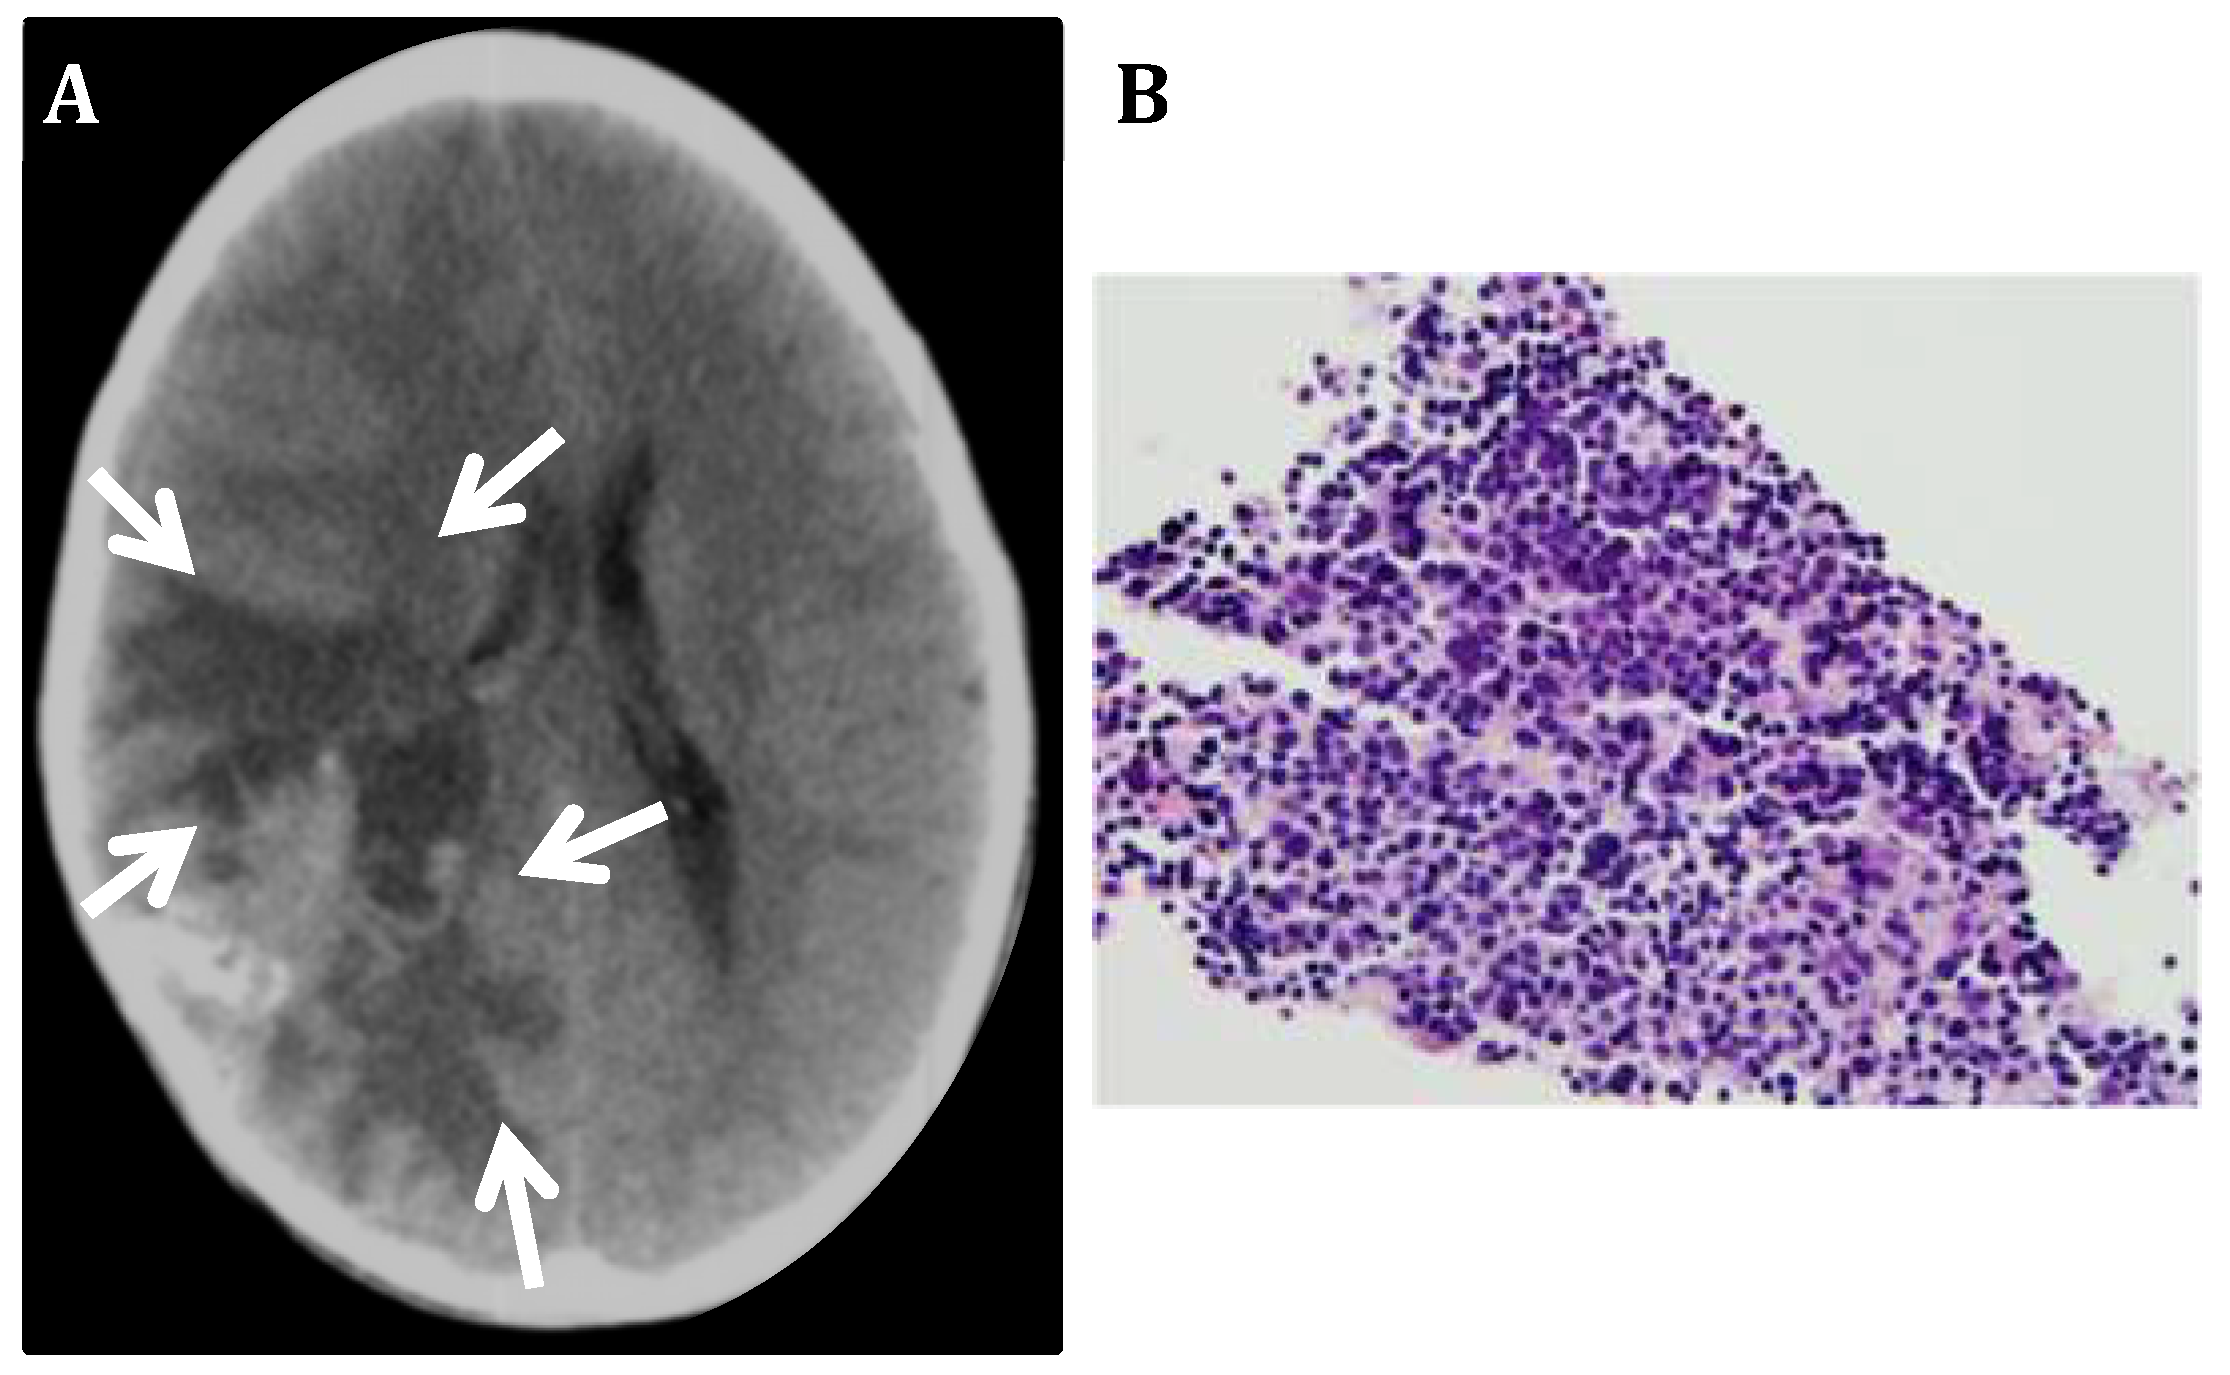

3.1. CNS Neuroblastoma